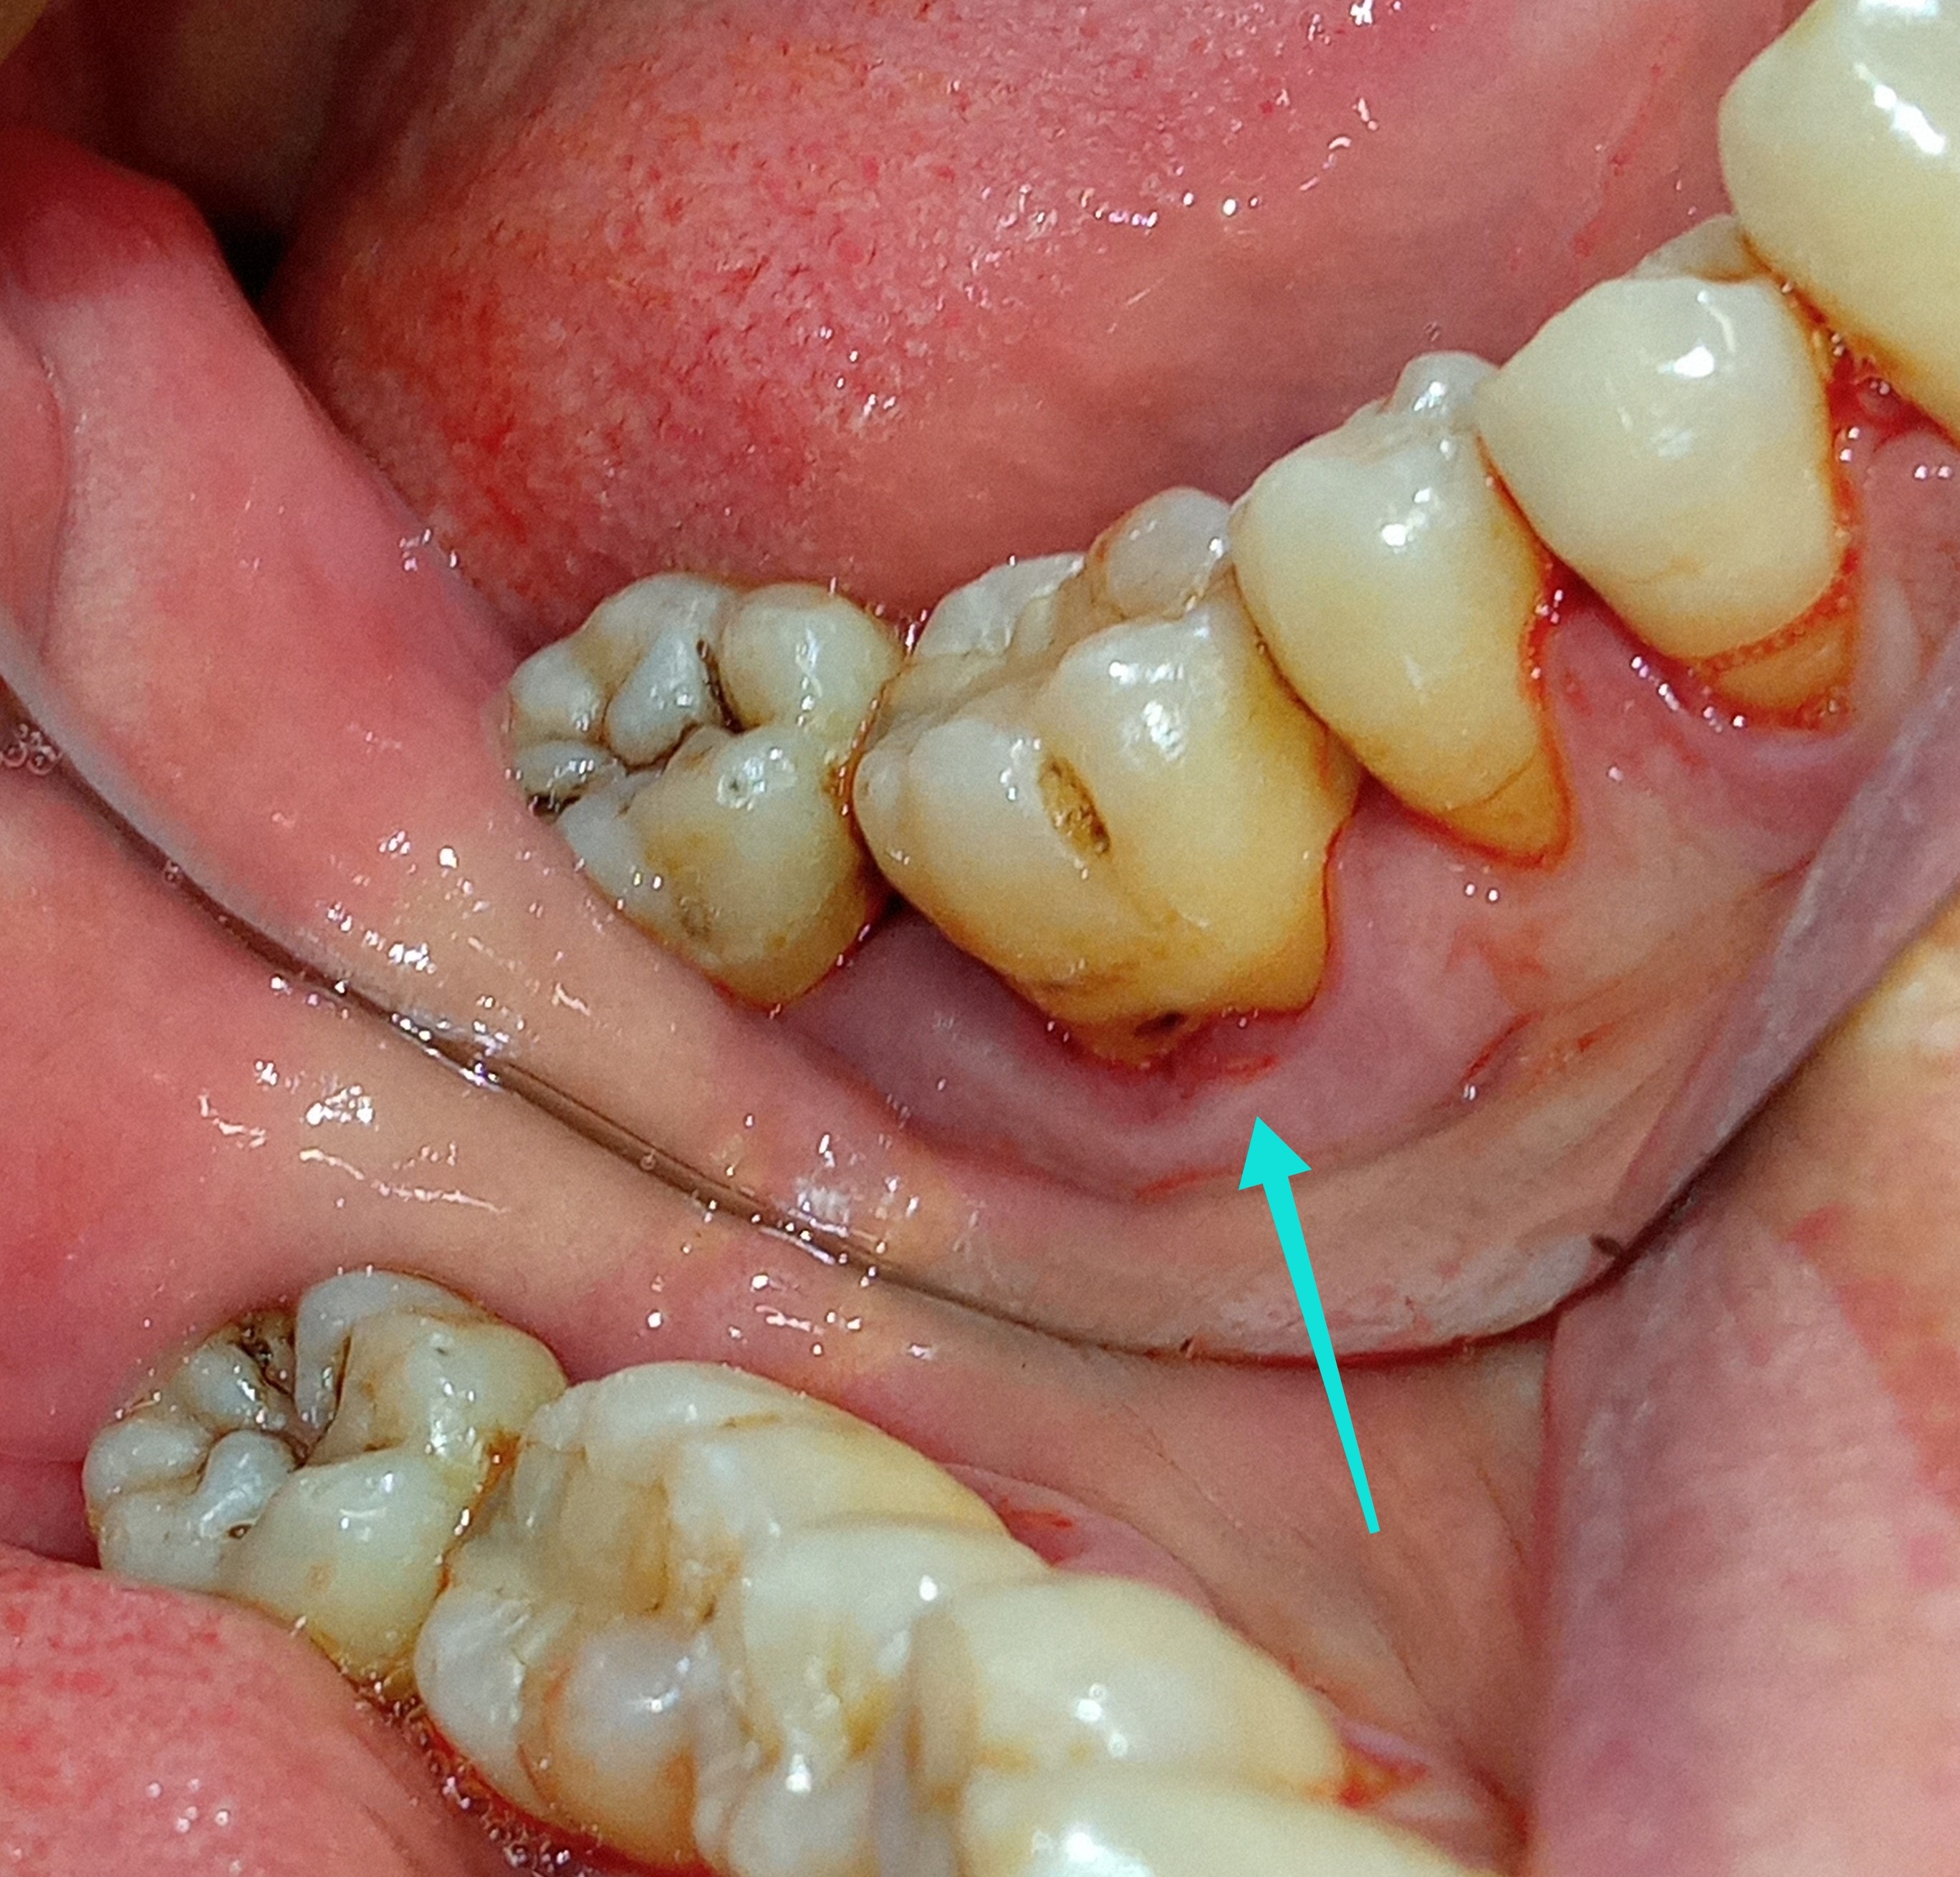

Ο ασθενής είχε μεγαλή τερηδονική αλλοίωση στον αυχένα και στην παρειακή επιφάνεια του πρώτου γομφίου. Το οδοντικό έλλειμμα αντικαταστάθηκε με αισθητικό λευκό σφράγισμα ρητίνης.

ΠΡΙΝ